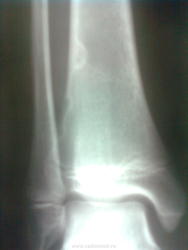

Пол пациента: Мужской пол Тип патологии: Другое Область исследования: Скелетно-мышечная система Методы исследования: Rg Мальчик, 14 лет, подвернул ногу, сделаны снимки. До травмы ни на что не жаловался. Была сделана другая голень - паталогических изменений не обнаружено. Мальчик активный, любит физкультуру. https://radiomed.ru/sites/default/files/styles/case_slider_image/public/user/16663/zobrazhennya2029.jpg?itok=b71ePDi6 ID:32035 Вс, 29/09/2013 - 21:13 #1 Vega Не на сайте Был на сайте: 3 месяцев 1 неделя назад Зарегистрирован: 22.01.2009 - 19:16 Публикации: 1087 Пусть любит дальше - с кортиальными дефектами можно и олимпийским чемпионом стать, они не помешают... Пнд, 30/09/2013 - 06:00 #2 Helios Не на сайте Был на сайте: 7 месяцев 2 недели назад Зарегистрирован: 06.08.2010 - 15:16 Публикации: 4417 Фиброзные кортикальные дефекты. Пнд, 30/09/2013 - 11:25 #3 Andriy Не на сайте Был на сайте: 11 лет 5 месяцев назад Зарегистрирован: 28.06.2012 - 14:24 Публикации: 82 Helios wrote: Фиброзные кортикальные дефекты. Это то-же, что очаги паталогической перестройки в местах прикрипления мышц, или что-то другое? Пнд, 30/09/2013 - 13:46 #4 Helios Не на сайте Был на сайте: 7 месяцев 2 недели назад Зарегистрирован: 06.08.2010 - 15:16 Публикации: 4417 Фиброзный кортикальный дефект, он же -неоссифицирующая фиброма. http://www.radiomed.ru/publications/kss-fibroznyi-kortikalnyi-defekt-pr-s Пнд, 30/09/2013 - 15:31 #5 Andriy Не на сайте Был на сайте: 11 лет 5 месяцев назад Зарегистрирован: 28.06.2012 - 14:24 Публикации: 82 Helios wrote: Фиброзный кортикальный дефект, он же -неоссифицирующая фиброма. http://www.radiomed.ru/publications/kss-fibroznyi-kortikalnyi-defekt-pr-s Огромное спасибо за ссылочку. Ср, 02/10/2013 - 18:49 #6 Соломин Виталий... Не на сайте Был на сайте: 5 лет 11 месяцев назад Зарегистрирован: 04.04.2012 - 21:47 Публикации: 1096 Vega wrote: Пусть любит дальше - с кортикальными дефектами можно и олимпийским чемпионом стать, они не помешают... Интересно. Не встречал такой точки зрения. А что бы Вы сказали, уважаемый коллега, вот по этому поводу: http://www.radiomed.ru/blogs/solomin-vitalii-yurevich/golen ?

Фиброзные кортикальные дефекты.

Фиброзный кортикальный дефект, он же -неоссифицирующая фиброма.